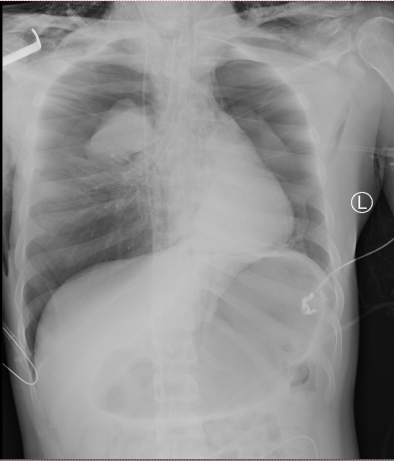

患者入院时虽神志尚清,但已出现声音嘶哑、颈部疼痛、胸闷气喘等危险信号,血氧饱和度持续下降。我院急诊团队评估后立即启动最高级别预警,迅速完成生命体征监护和检查的同时,敏锐地察觉到患者颈部正在快速肿胀,这是皮下气肿的典型表现,预示着气道可能存在严重破损。我院耳鼻喉科专家通过喉镜探查,做出了关键性判断:高度怀疑喉软骨骨折、气管断裂。后续CT检查结果印证了这一判断,患者双侧颌面部、颈部、胸部乃至纵隔内出现了大量积气。更危急的是,断裂处漏出的气体已形成双侧张力性气胸,双肺被压缩均近50%,心脏和大血管严重受压,情况十分危急!

患者气道严重变形导致常规的气管插管效果不理想,时间就是生命!急诊科、耳鼻喉科、麻醉科医生当机立断,决定立即行床旁紧急气管切开术。在濒死的危急关头,手术团队临危不乱,以精湛的技术迅速建立了新的“生命通道”,呼吸机得以顺利接上,为后续抢救赢得了最宝贵的“黄金时间”。与此同时,胸外科团队火速到位,为患者施行双侧胸腔闭式引流术。当引流管置入胸腔的瞬间,大量高压气体喷涌而出,被严重压缩的肺脏得以复张,心脏的压迫即刻解除,患者的氧合指标得到了极大改善。